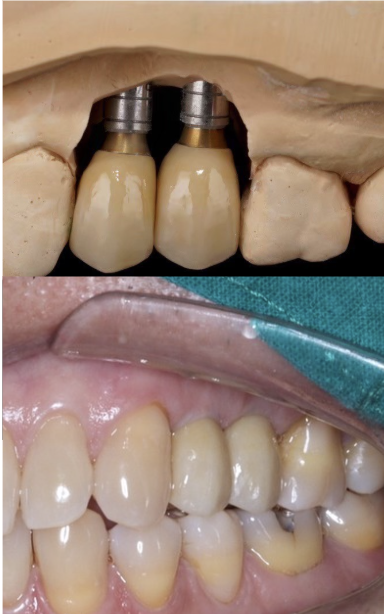

ไม่มีฟันเคี้ยว ครอบเก่าฟันหน้าไม่สวย คุณหมอบอกต้อง

ทำใหม่เกือบทั้งปาก ครอบฟัน 20 ซี่ รากเทียม 4 ซี่ ทำเสร็จแล้วคุ้มค่ามาก ยิ้มสวย ใช้งานได้ดีเลยค่ะ — คุณนิจรินทร์